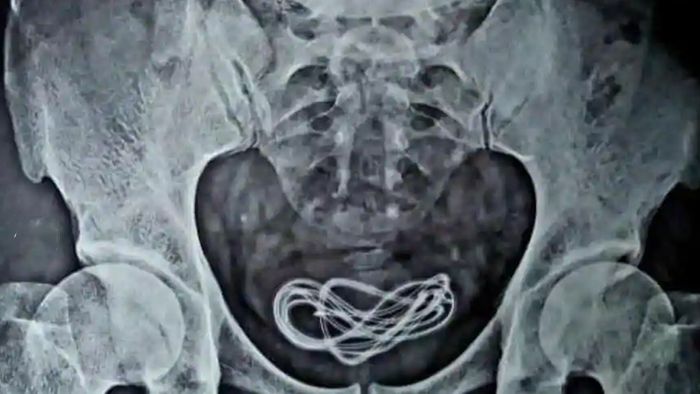

He further added that the matter came to light after conducting an X-ray in the operation theatre. “The X-ray revealed that the cable was in the person’s urinary bladder,” he said while adding that the cable was removed successfully.